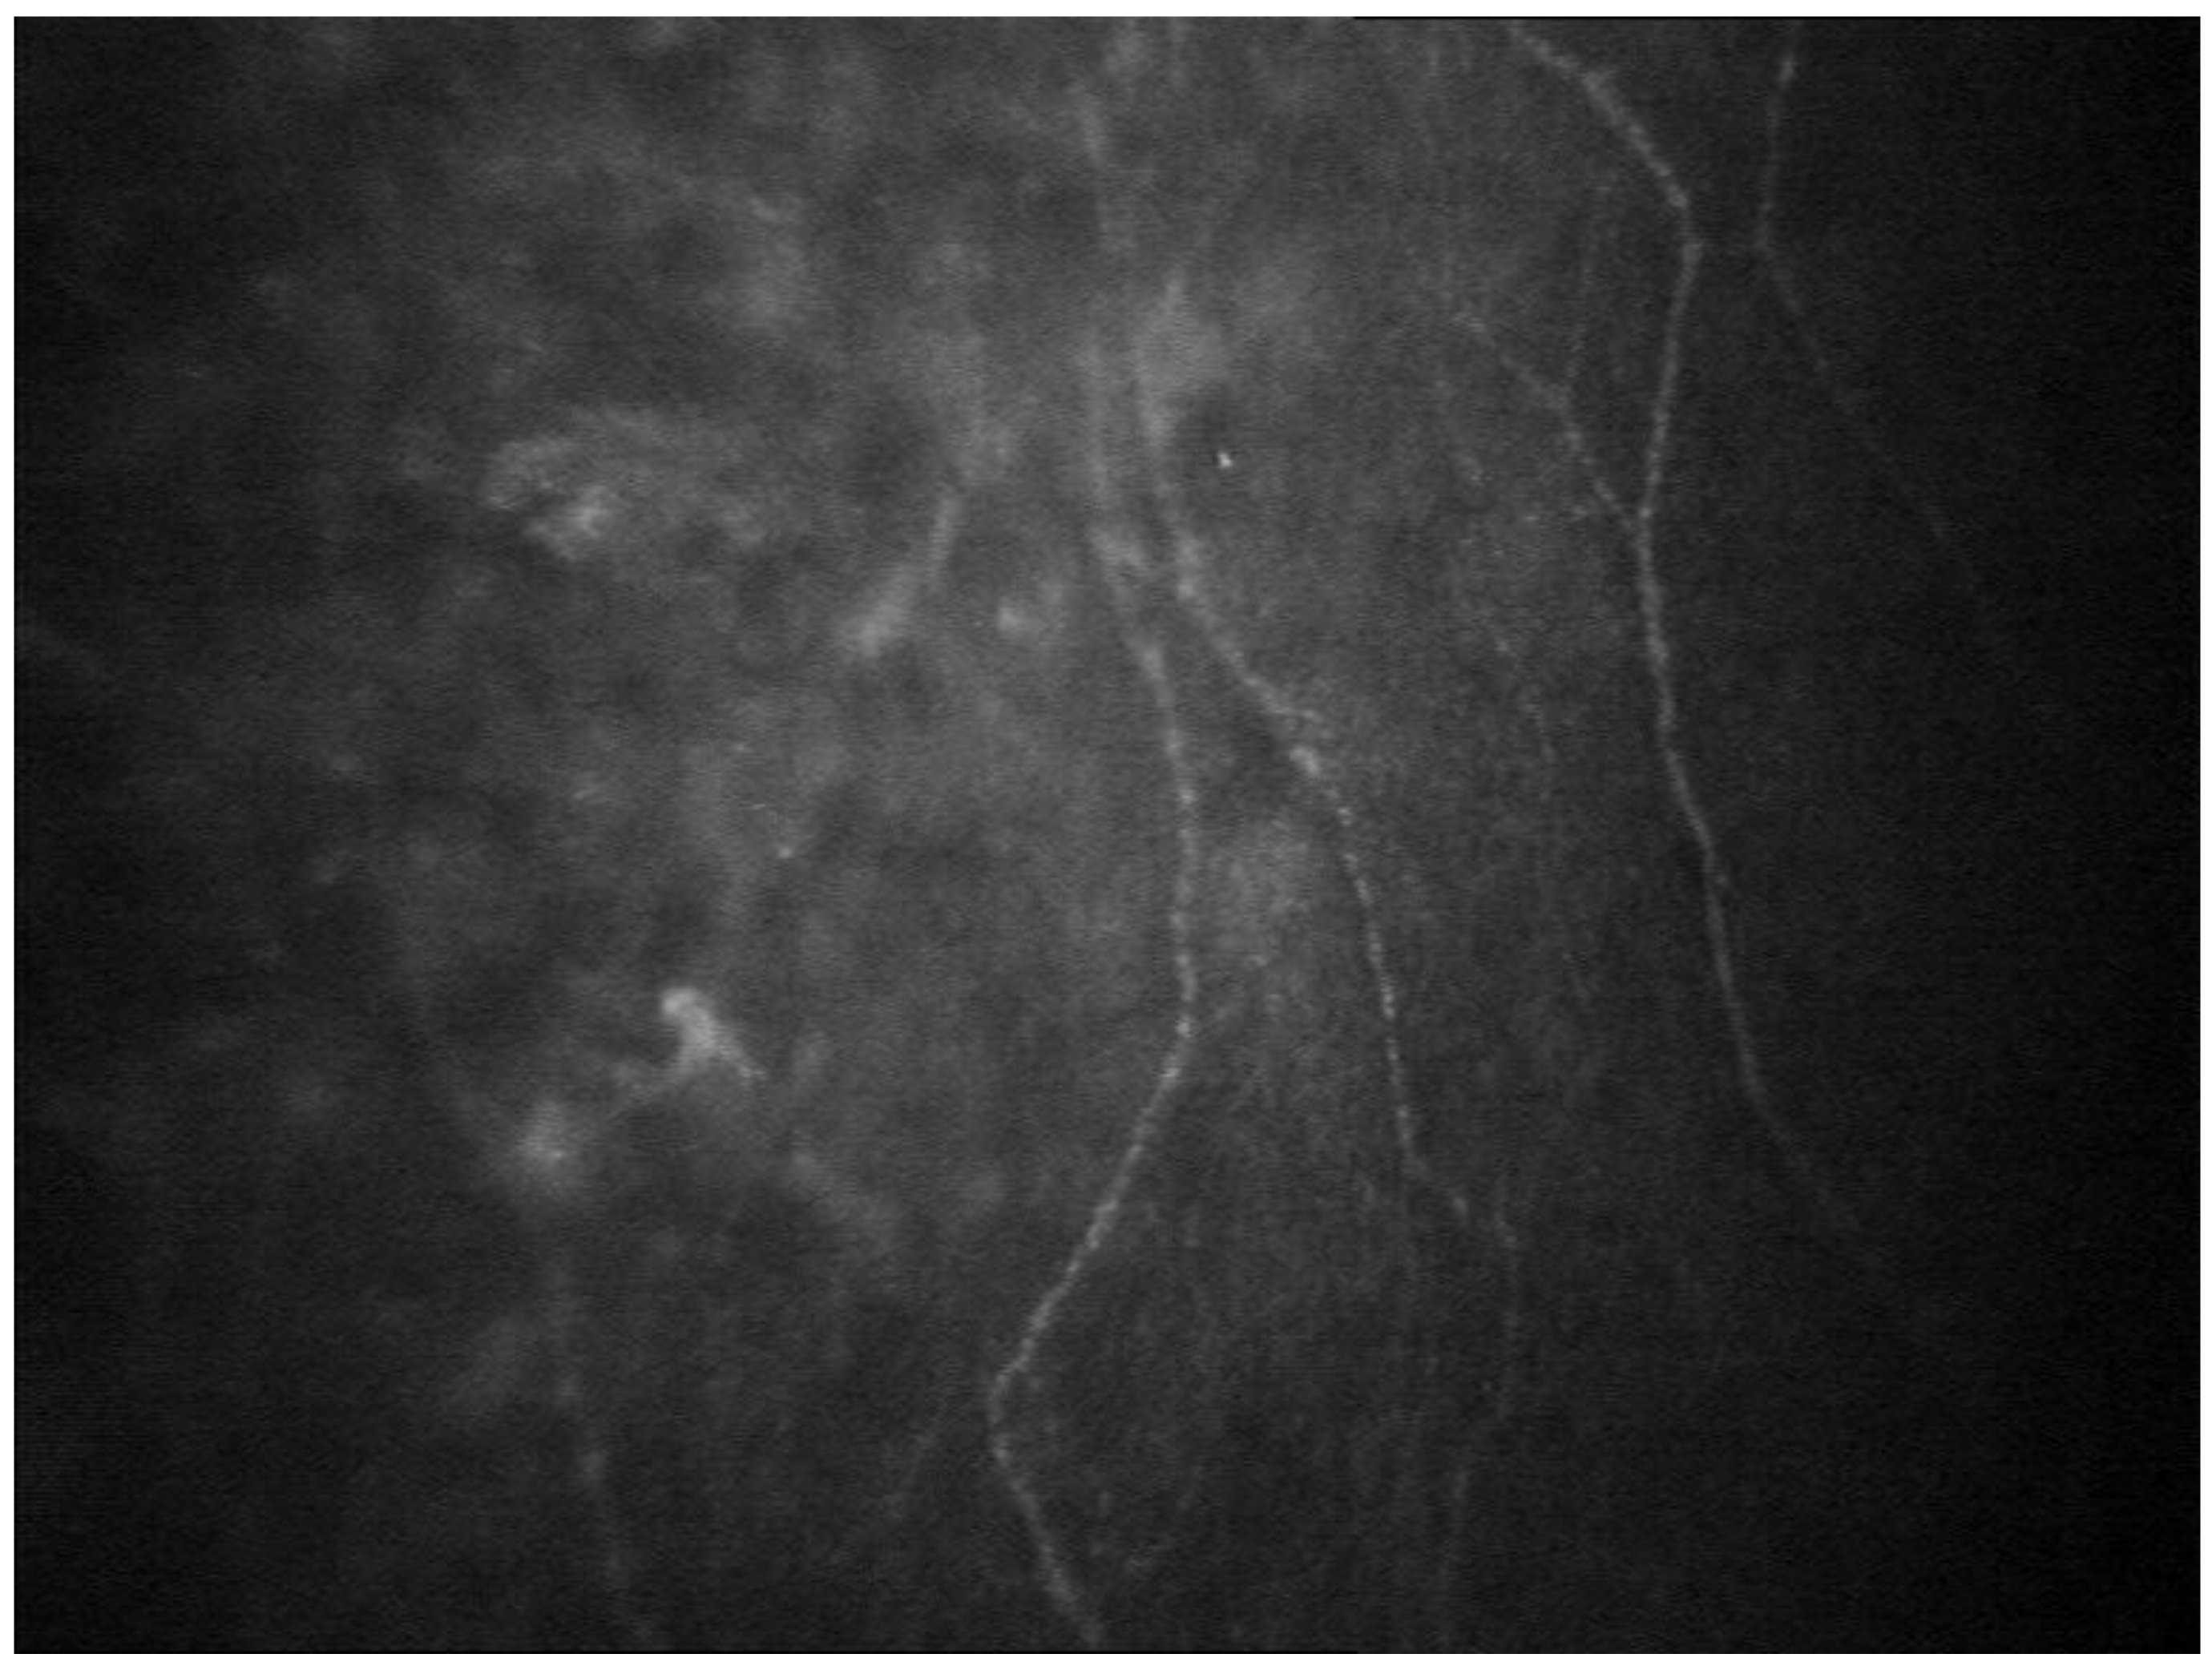

- Chorioretinal Vascular Changes

- Rousseau, A.; Terrada, C.; Touhami, S.; Barreau, E.; Rothschild, P.-R.; Valleix, S.; Benoudiba, F.; Errera, M.-H.; Cauquil, C.; Guiochon-Mantel, A.; et al. Angiographic Signatures of the Predominant Form of Familial Transthyretin Amyloidosis (Val30Met Mutation). Am. J. Ophthalmol. 2018, 192, 169–177. [Google Scholar] [CrossRef] [PubMed]